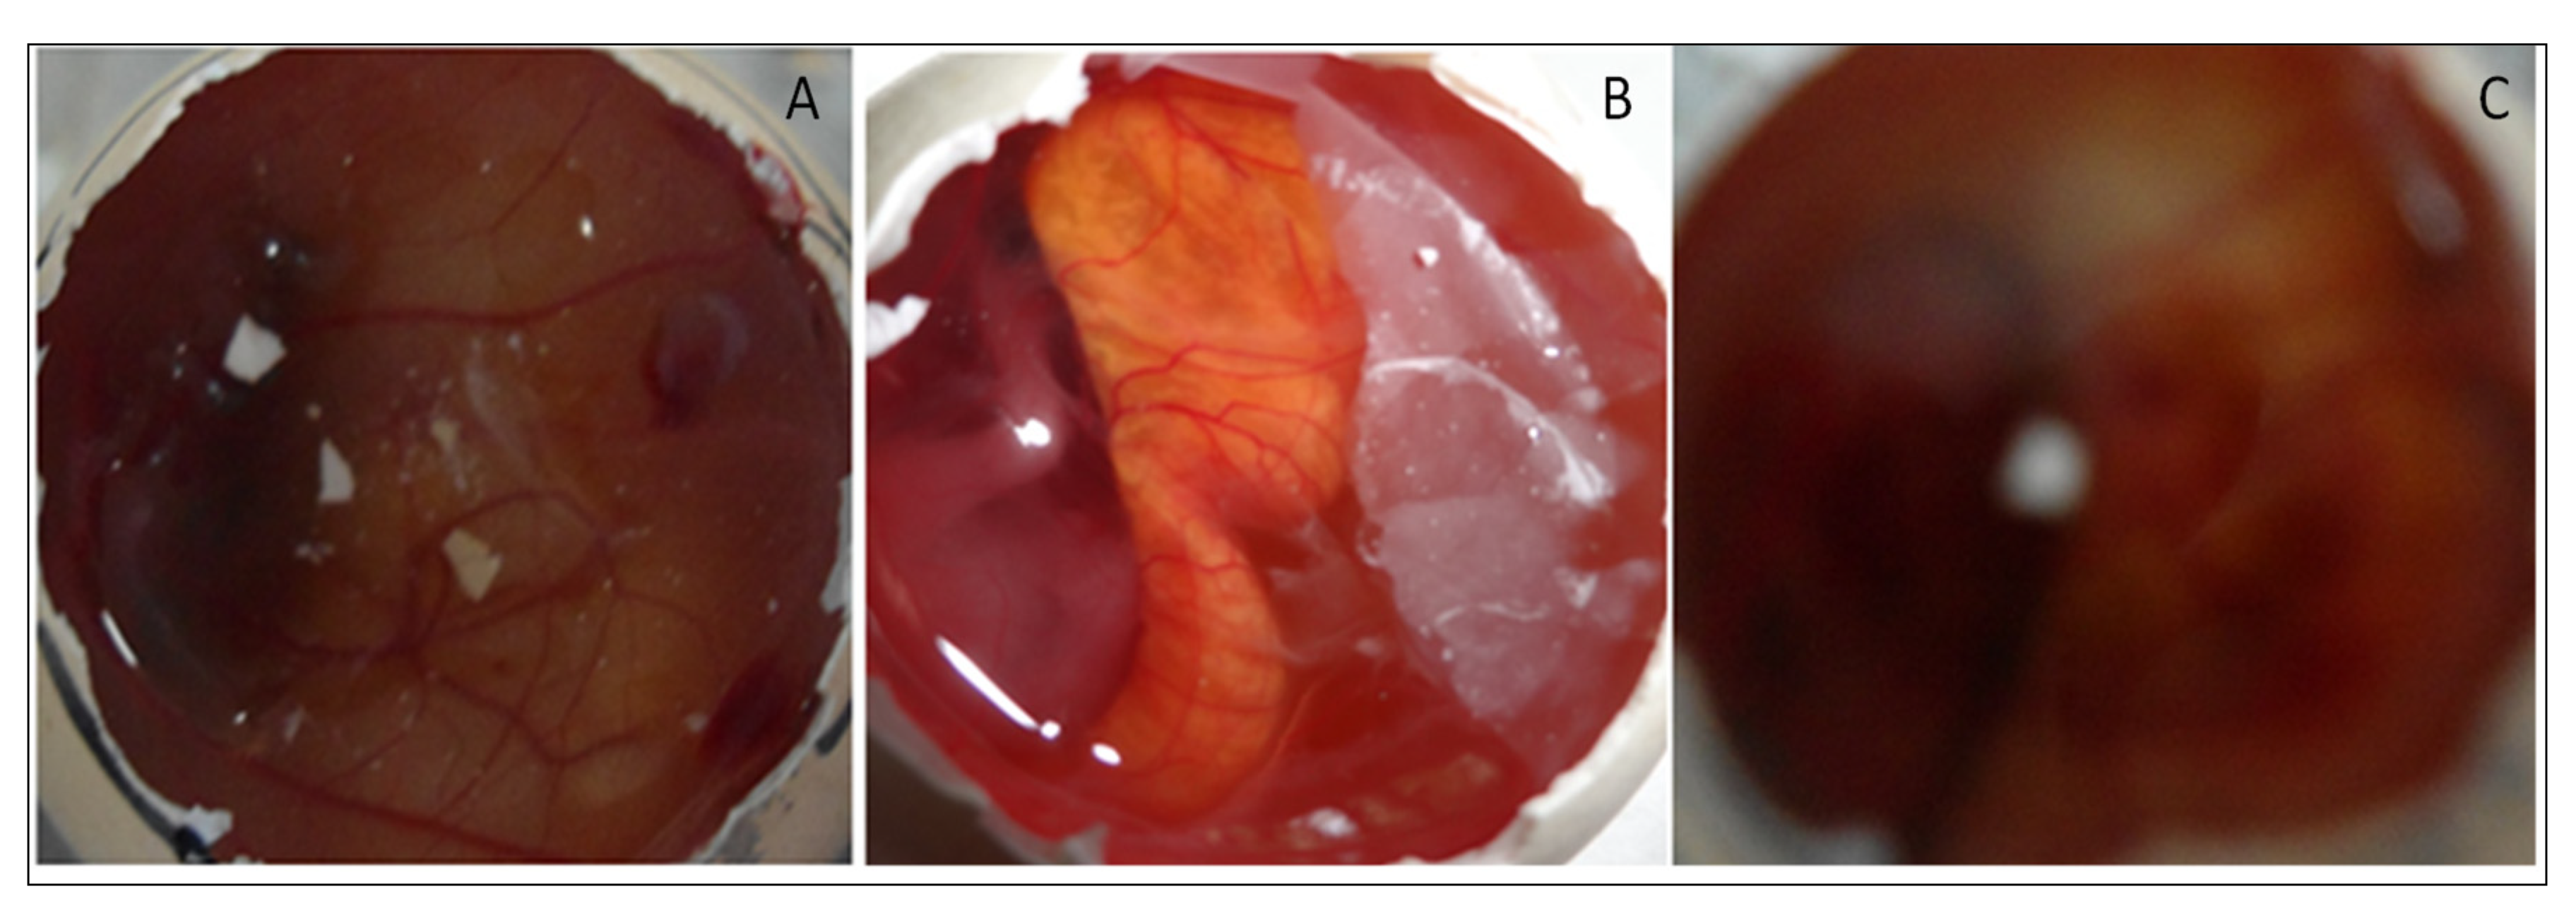

4.8.8. HET CAM Irritation Study

4.8.9. Sterility and Isotonicity Study